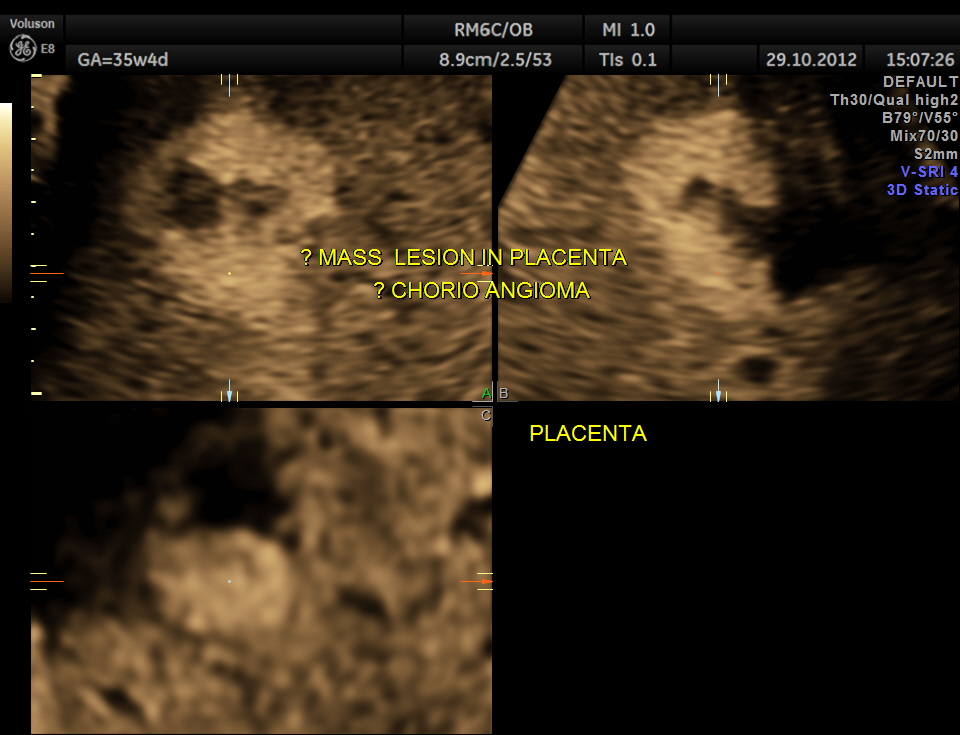

The scan was done around the 35 weeks.The following images were seen .

apart from this the placenta showed a few lakes and a localised mass , probably chorio angioma